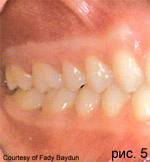

Гингиво-пародонтальная атрофия

Гингиво-пародонтальная атрофия - это регресс десны и альвеолярной кости на выпуклостях корня в буккальной, лингвальной и палатинальной проекциях. До сих пор это состояние обозначалось как десневая рецессия. Понятие "гингиво-пародонтальная атрофия" - понятие широкое, так как первичное отсутствие кости альвеолярного отростка над выпуклостями корня в виде костной дегисценции (частичного обнажения участков корня зуба) определяет картину болезни. Клинически выявленные процессы десневой рецессии могут быть генерализованными или локальными. Часто они обобщаются с типичными фиброзными опухолевыми утолщениями краев (гирлянды МакКолла) и с образованием узких расщелин (расщелин Штильманна). Гингиво-альвеолярная атрофия возникает первично после прорезывания зубов через генетически заданное неправильное соотношение размеров, формы и признаков искривления корней с окружающим альвеолярным отростком и толщиной кости. После прорезывания зубов под слизистой оболочкой образуются клинически не выявляемые костные дегисценции, а также фенестрации (свищи) над корнями. В период функционирования зуба и с увеличением возраста наступает истончение десневой манжеты и трофические нарушения, которые особенно увеличиваются при растягивании связок и при слишком узкой прикрепленной десне. К прогрессированию также приводят экзогенные раздражения, такие как хроническая механическая травматизация при чистке зубов и при проведении других методов ротовой гигиены.